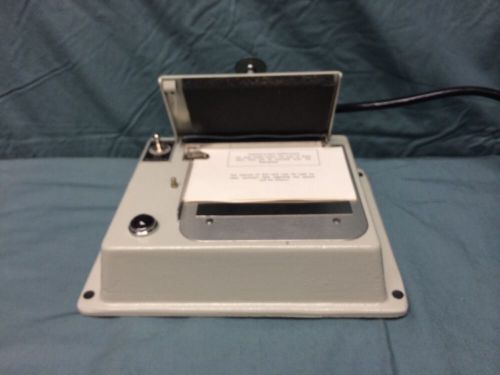

Xray ID PRINTER - Picker - Model 390032 (Brand New) with Transformer